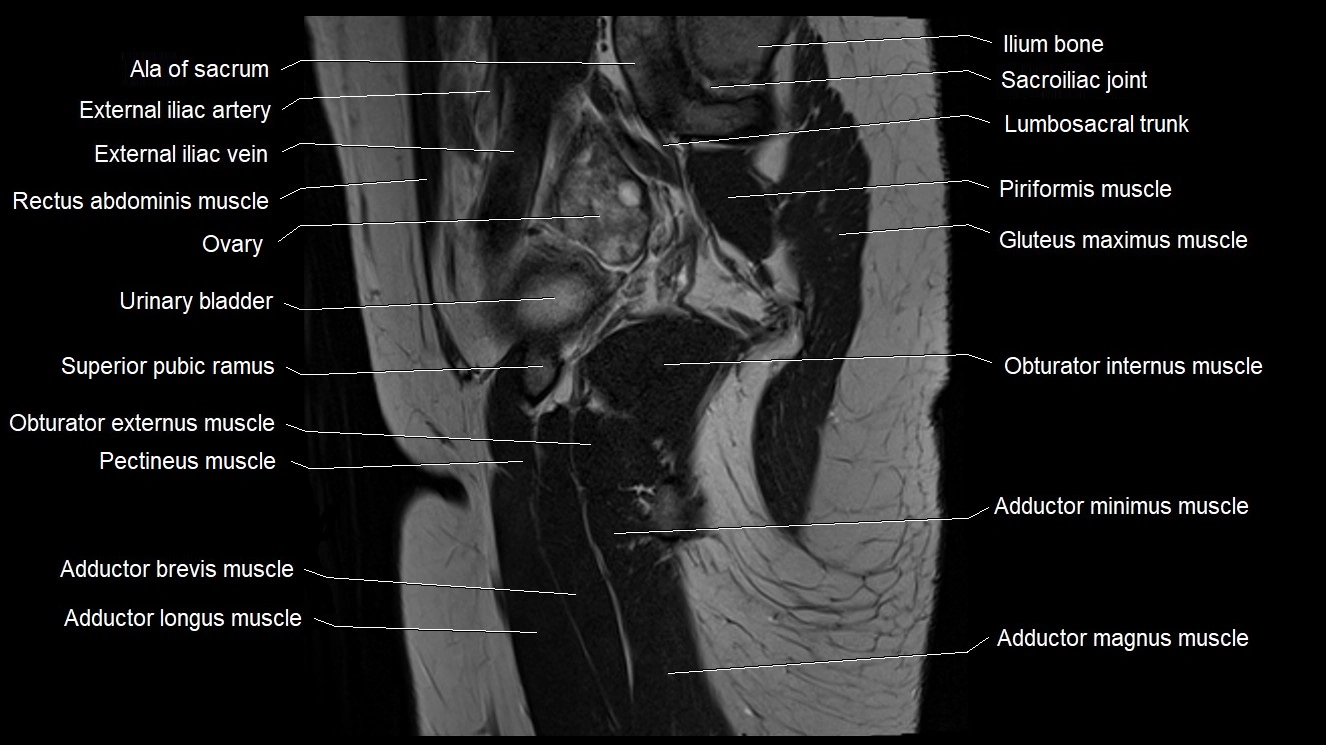

- Ala of sacrum

- Body of ischium

- Ilium bone

- Lumbosacral trunk

- Mesorectal fascia

- Obturator externus muscle

- Obturator internus muscle

- Ovaries

- Pectineus muscle

- Rectum

- Sacroiliac joint

- Sacrospinous ligament

- Superior pubic ramus

- Superior rectal vein

- Superior vesical artery

- Urinary bladder

- Uterus